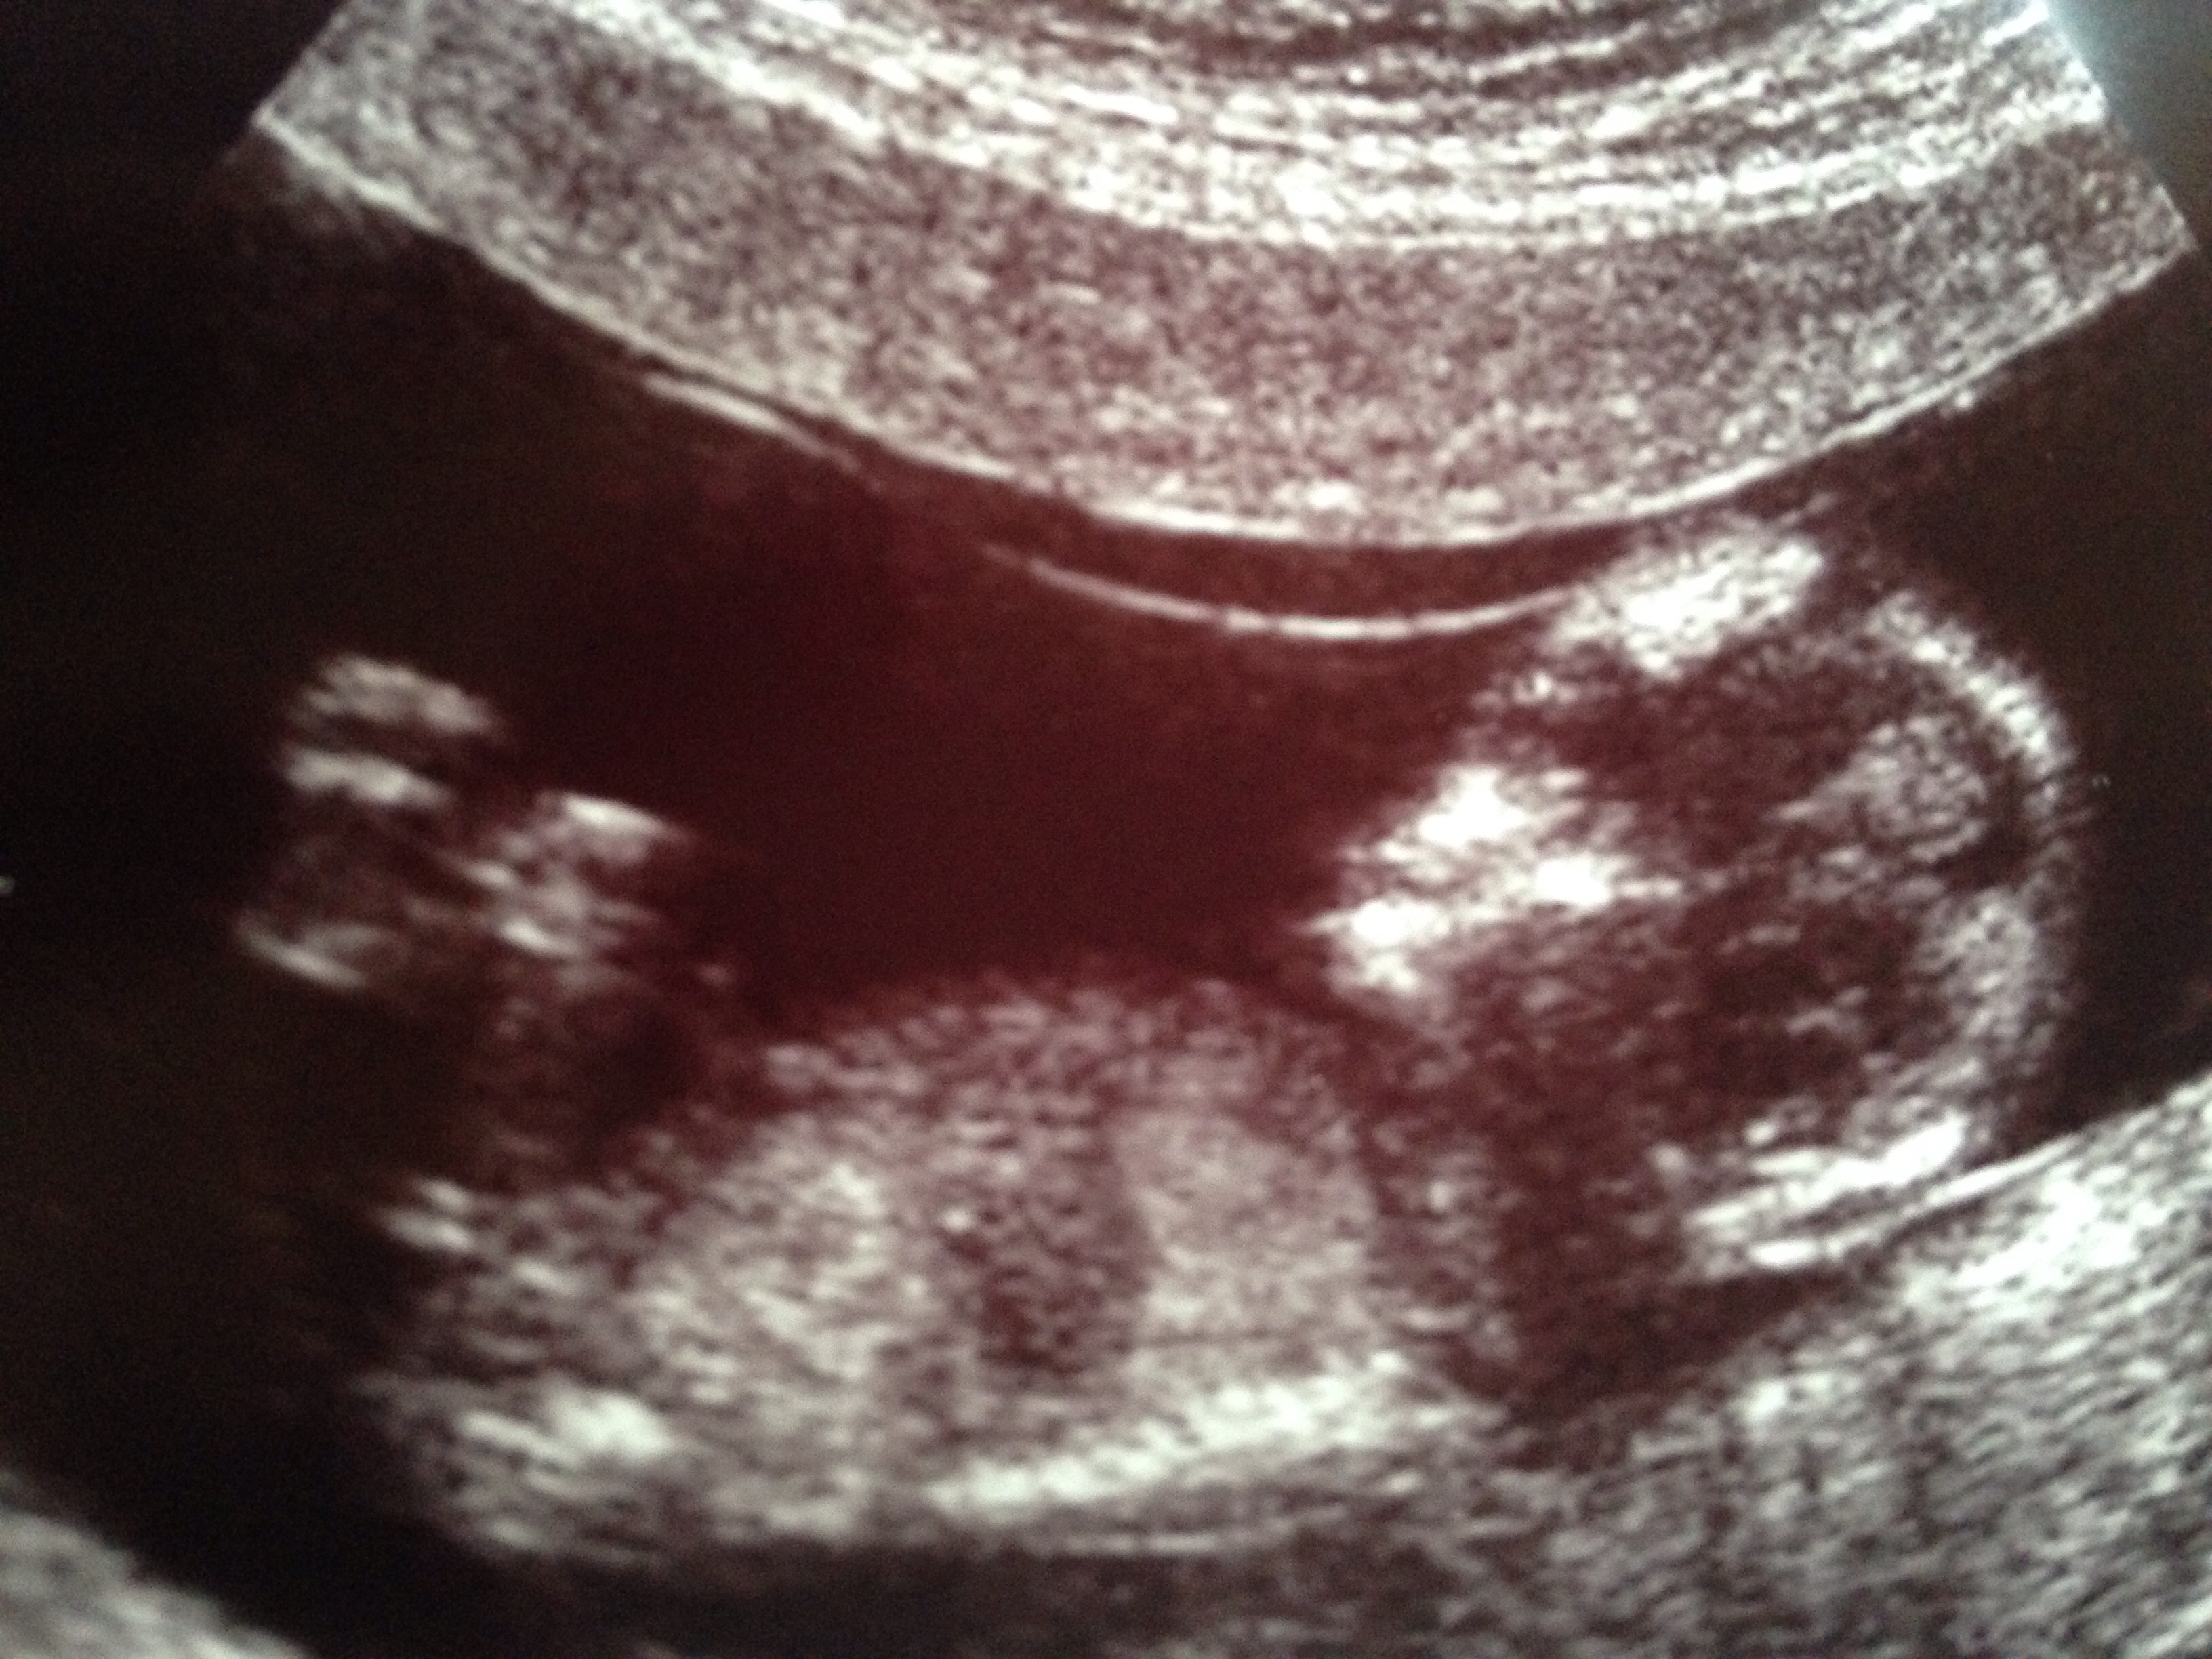

gestation is 13wks - please tell me what you all think?

I'd say boy [emoji4]

looks blue to me

Boy

I would guess boy too; the angle isn't particularly great however the nub is very obvious for 13 weeks. Good luck to her! :) xx

I thought girl from first nub pic. But last nub pic looks more angled up- boyish